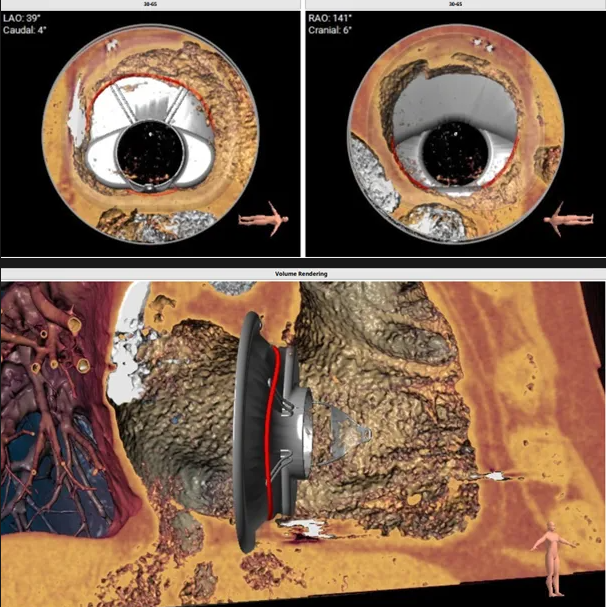

瓣膜植入模擬

術中經食道超聲輔助下可見LuX-Valve Plus夾持件順利抓捕瓣葉,室間隔錨定位置良好,假體瓣膜整體錨定狀態穩固。